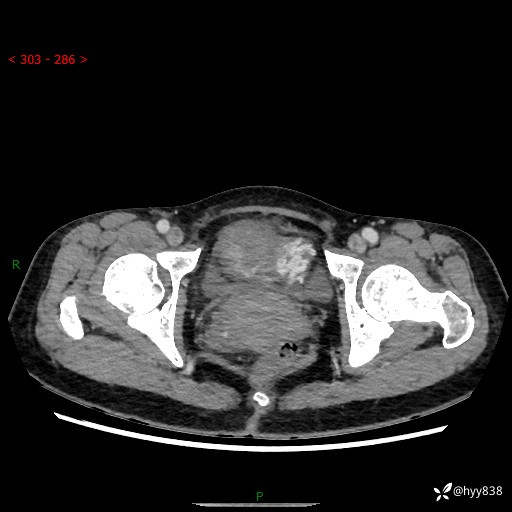

【患者信息】:女,50岁

【主诉】:外院超声发现腹盆肿块,为进一步诊治来我院,门诊已“盆腔肿块”收入院。

腹盆CT平扫+增强

【临床诊断】:盆腔肿瘤